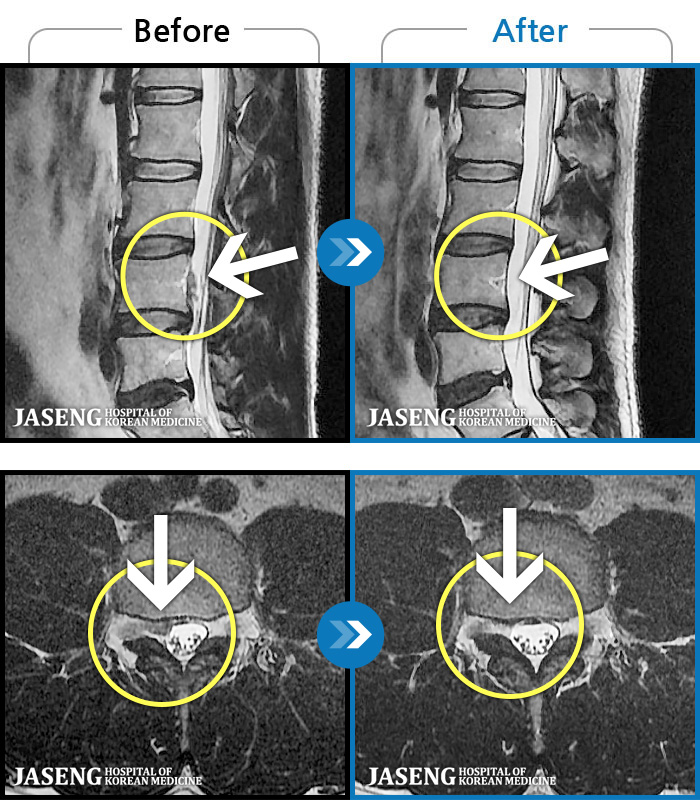

1,228건의 MRI 전후 사진으로 터진 디스크 흡수 사례를 확인하세요.

※ 환자분에게 사전 동의를 받아 동일 조건에서 촬영되었으며, 개인에 따라 치료 후 부작용이 발생할 수도 있으니 사전에 의료진과 상담 후 치료를 진행하시기 바랍니다.

※ 환자분에게 사전 동의를 받아 동일 조건에서 촬영되었으며, 개인에 따라 치료 후 부작용이 발생할 수도 있으니 사전에 의료진과 상담 후 치료를 진행하시기 바랍니다.